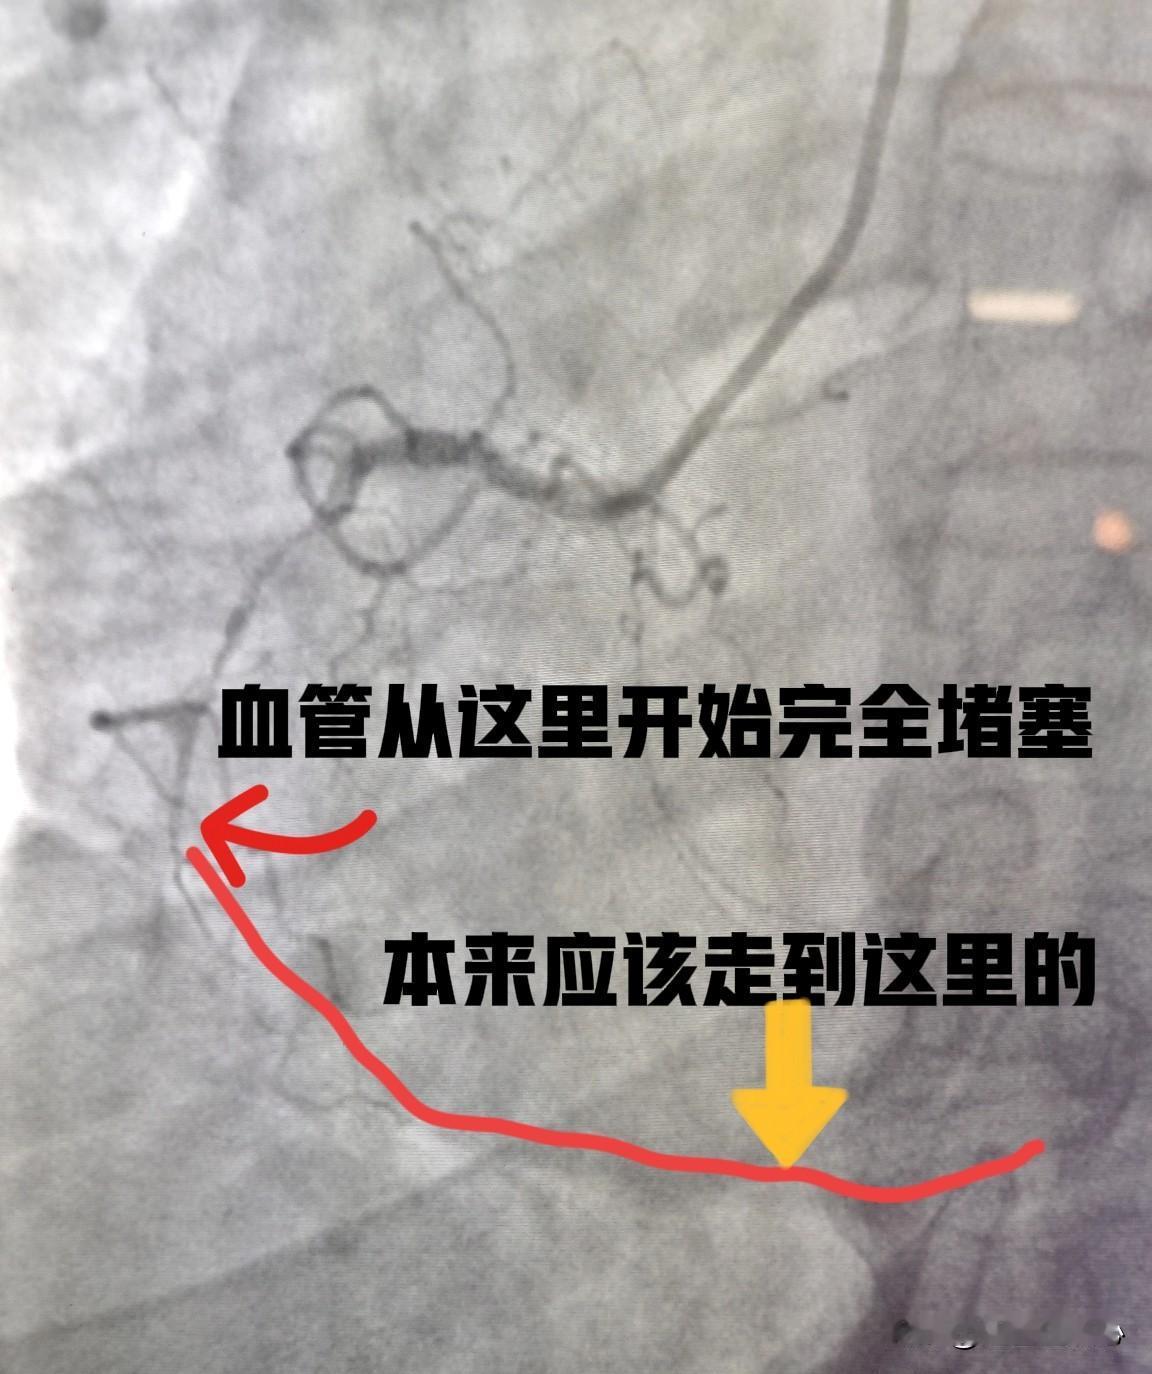

这是一个53岁男性患者,做了冠脉CTA检查发现右冠状动脉重度狭窄,入院以后复查了冠脉造影(如图1),显示右冠近段重度狭窄,远端完全堵塞了,远端血管无法供血。选用SAL0.75的指引导管,在微导管的支持下,用导丝通过病变(如图2)。直径1.5mm的球囊扩张近段重度狭窄段后,造影发现远端血流仍然没有显示(如图3)。这时直接冠状动脉内注射了硝酸甘油,精准给药,直达冠状动脉。几秒钟后再次造影发现,远端血管瞬间通畅,血流完全恢复。最后在近段植入2枚支架(如图4)。